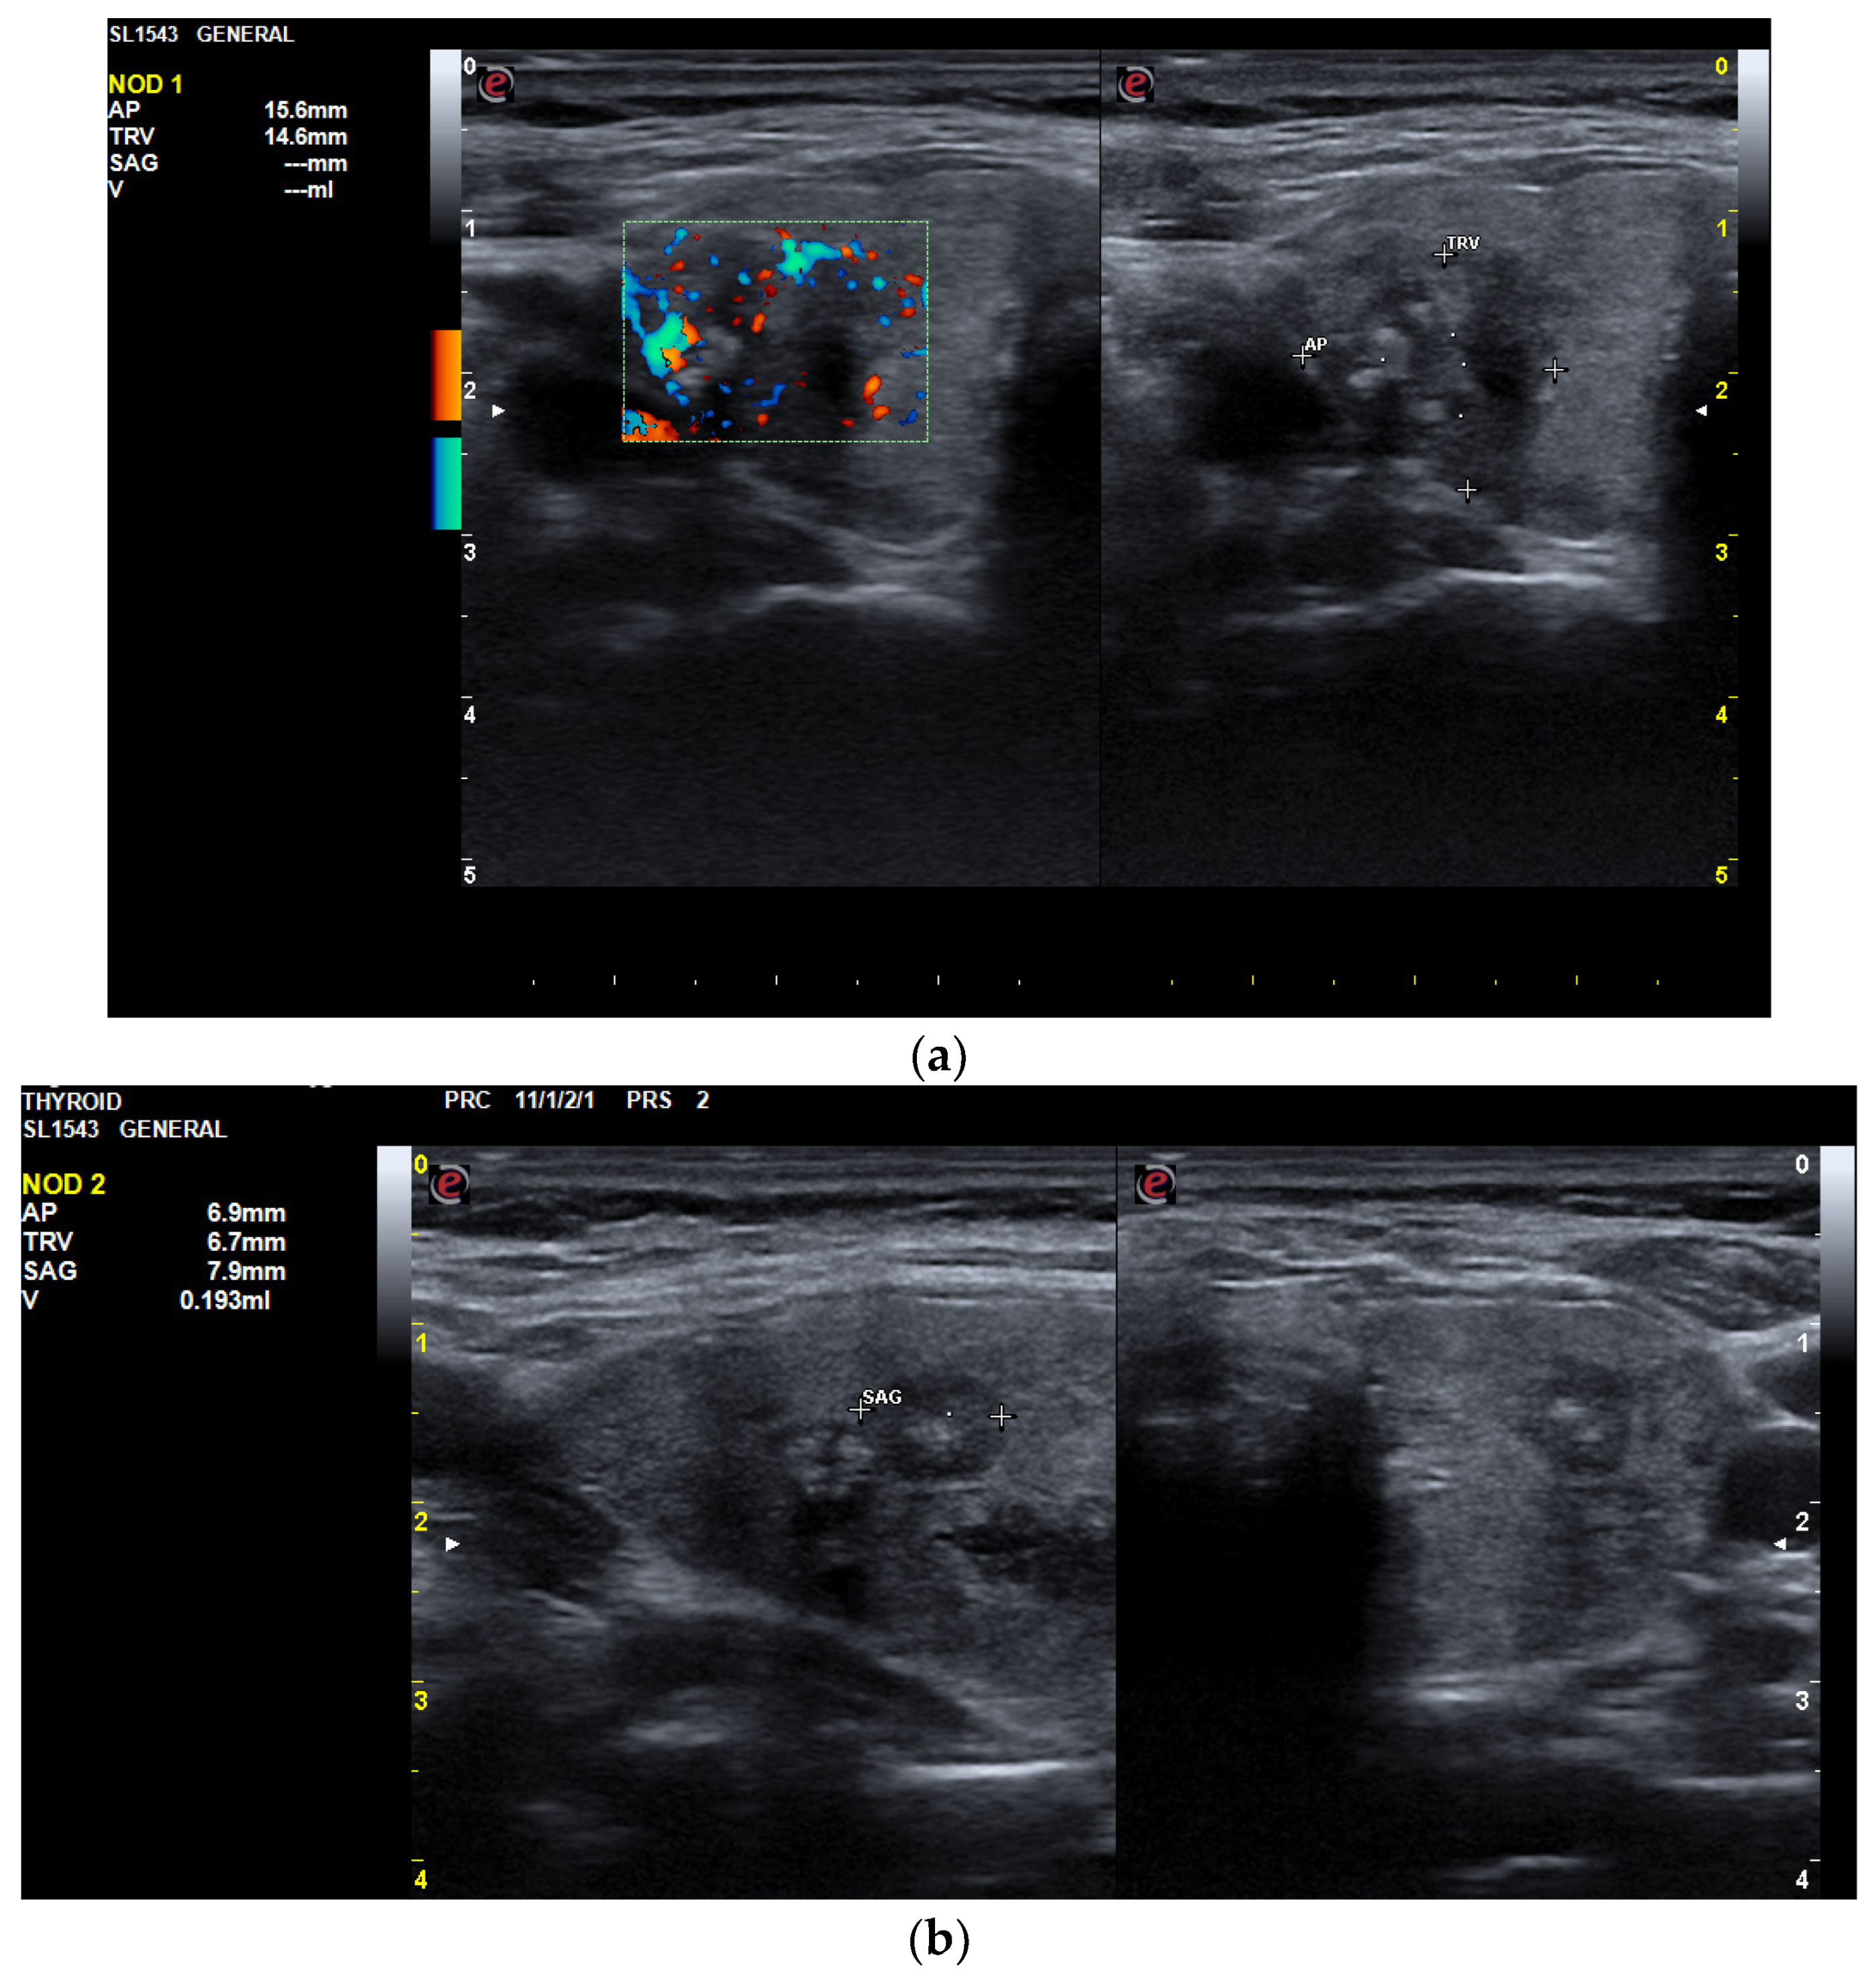

3.1.2. Thyroid Ultrasound

3.2.2. Thyroid Ultrasound

3.3.2. Thyroid Ultrasound